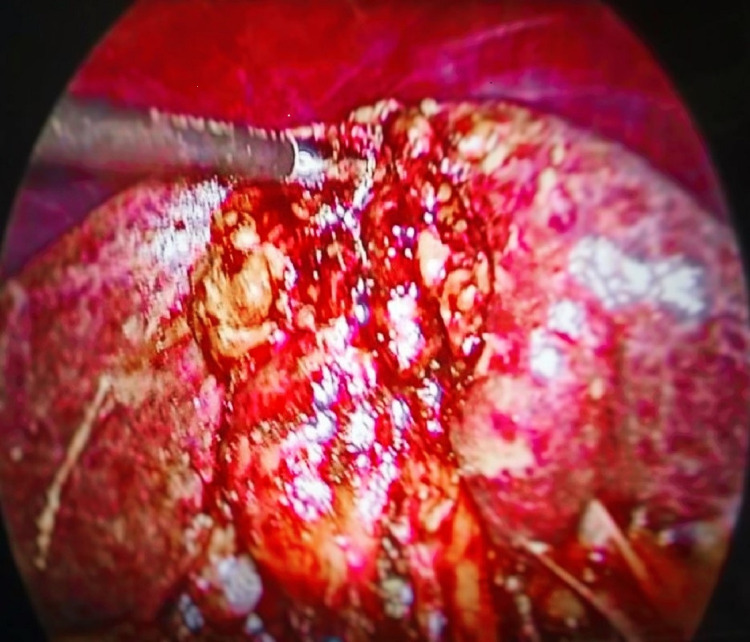

Pericholecystic adhesions (Figure 1), contracted gallbladder (Figure 2), gallbladder wall thickening, and frozen Calot’s triangle were observed significantly more among diabetic patients in comparison with nondiabetic patients. However, impaction of stone in Hartman’s pouch was present in six patients (8%) in the diabetic group in comparison with four patients (5.3%) in the nondiabetic group (Table 1).

Subtotal cholecystectomy was done in four patients (5.3%) in the diabetic group and two patients (2.6%) in the nondiabetic group. The reason for subtotal cholecystectomy was frozen Calot’s anatomy in both groups of patients. Conversion to open procedure was done in 4% of diabetic patients due to dense adhesions, altered anatomy, and inability to proceed to laparoscopy. The mean duration of surgery was taken as 90 minutes, and it exceeded in 52 diabetic patients (69.3%) and 27 nondiabetic patients (36%). A drain was given in 14 patients (18.6%) in the diabetic group and nine patients (12%) in the nondiabetic group. A tube drain was inserted in all patients with subtotal cholecystectomy and open conversion. Recovery from anesthesia was more than 20 minutes in 45 patients (60%) in the diabetic group and 18 patients (24%) in the nondiabetic, which was statistically significant. The reason for delayed anesthesia recovery was various intraoperative and metabolic factors in diabetes. Intraoperative injury was not reported in CBD or surrounding organs (Figure 3).

The duration of surgery of diabetic patients was significantly higher than nondiabetic patients because of more adverse intraoperative findings. Intraoperative findings such as pericholecystic adhesions, contracted gallbladder, thickened wall, impacted stone in Hartman’s pouch, and frozen Calot’s anatomy are more often seen in diabetics. All these factors contribute to operative difficulty, increased time, complications, and also open conversion. This was reflected in our study populations, except for frozen Calot’s anatomy, similar in both groups. Different pain sensations and less sensitivity in diabetic neuropathy also result in a delayed diagnosis [ref. 13]. This leads to repeated silent attacks of cholecystitis.

The intraoperative decisions for modification were subtotal cholecystectomy and open conversion. Subtotal cholecystectomy was done in obscured Calot’s triangle anatomy, where a critical view of safety could not be achieved and it is a better alternative. In a meta-analysis, Elshaer et al.’s results were in favor of laparoscopic subtotal cholecystectomy [ref. 14]. The only problem was more bile leak and a possibility of stone formation of retained Hartman’s pouch. In our small series of a total of six patients, four patients were diabetic and the remaining two patients were nondiabetic, suggesting the more operative difficulty in diabetes. The possibility of stone formation is dependent on the residual infundibulum, more with 3-4 cm, as it forms the pouch and can be minimized if the distance is maintained within 1 cm [ref. 15]. Fenestration is an alternative method of ligating the cystic duct from inside the gallbladder, although less often preferred. Open conversion is considered as the last option when the gallbladder cannot be grasped or retracted in a buried gallbladder compromising all safety measures of cholecystectomy.